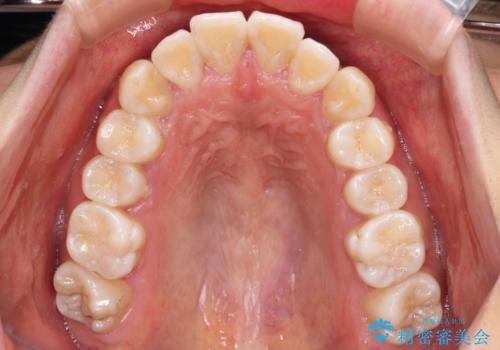

- 全体的な歯列の叢生を気にして来院された患者様です。

奥歯の咬み合わせを見ると、片方は上顎が下顎に対して相対的に前方にある状態でした。

咬み合わせを改善するためには、上顎臼歯を後方に移動させた咬み合わせにする必要があります。

インビザライン単体で改善することも可能ですが、ディープバイトのためインビザライン単体で達成する可能性が低いと考えられたため、カリエール・ディスタライザーという補助装置を併用して、より確実性を上げることとしました。

奥歯の咬み合わせ改善後に、インビザラインにて歯列を整えることとしました。